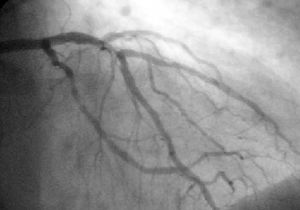

رسم القلب التاجي (آشعة سينية بتباين معتم إشعاعياً في الشرايين التاجية) تظهر الدورة التاجية اليسرى. الشريان التاجي الرئيسي الأيسر (LMCA) القاصى يبدو في يسار الربع الأعلى من الصورة. فروعه الرئيسية (وهي أيضاً واضحة) هي الشريان المنعطف الأيسر (LCX)، الذي يمتد من أعلى إلى أسفل في البداية ثم إلى المنتصف/القاع، والشريان النازل الأمامي الأيسر (LAD)، الذي يمتد من اليسار إلى اليمين في الصورة ثم ينزل إلى منتصف الصورة ليظهر تحت LCX القاصى. الشريان LAD، كالمعتاد، له فرعان قطريان كبار، ينشآن في منتصف-أعلى الصورة ويمتدا نحو منتصف/يمين الصورة.